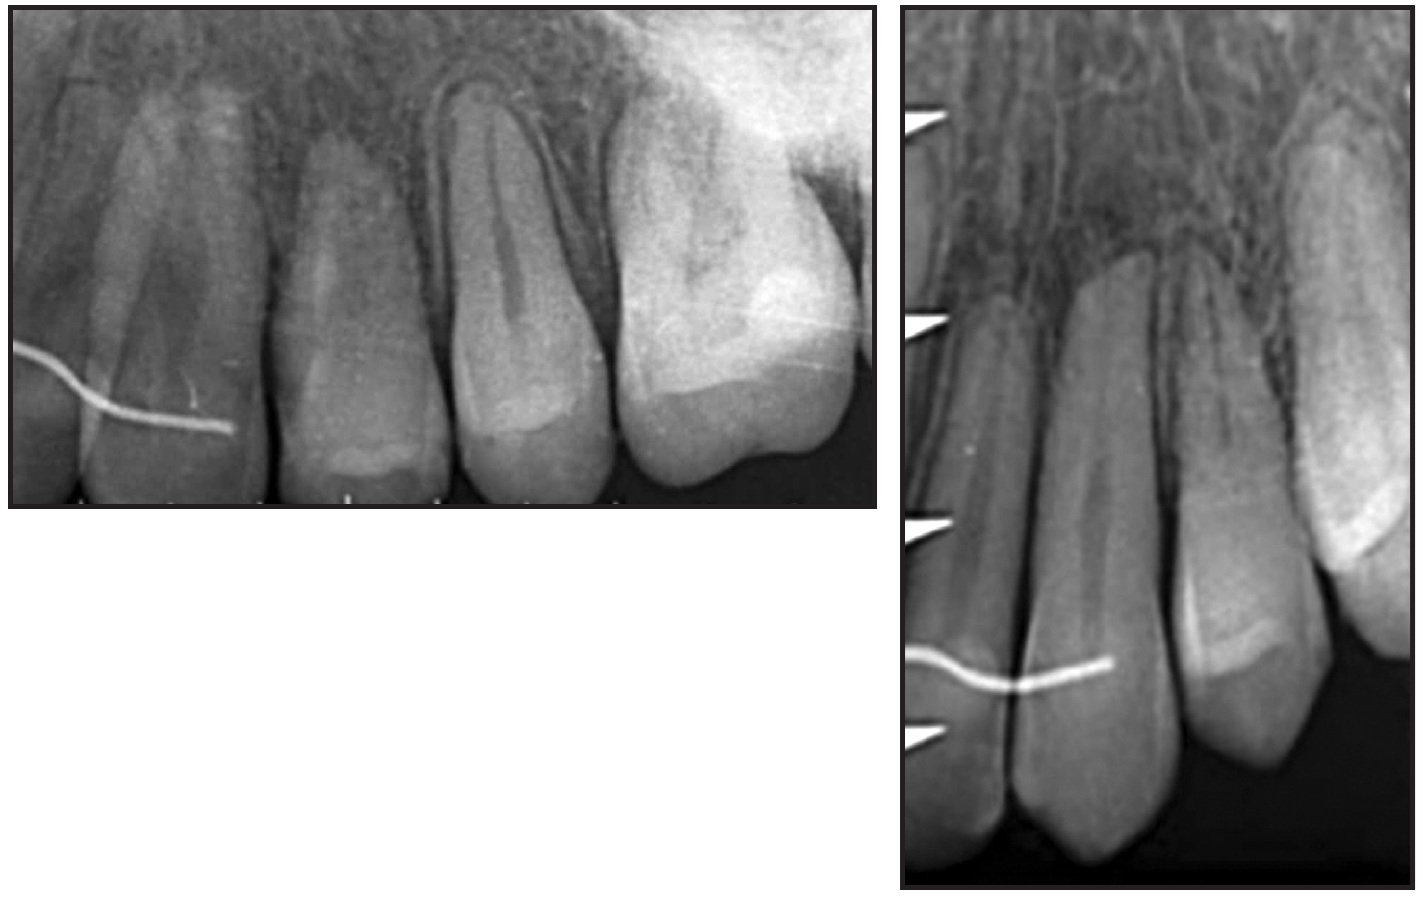

Several options are available to manage transposed teeth, including early interceptive treatment by guided eruption, extraction of one transposed tooth followed by orthodontic space closure, and alignment of the teeth in the transposed locations followed by selective reshaping or composite build-ups. Orthodontic correction of dental transpositions is more complicated.15,17-26 Since the alveolar ridge is usually not wide enough to accommodate two dental roots moving past each other, root parallelism will likely be less than ideal, and gingival recession may occur as the roots move outside the alveolar housing (Fig. 1). Alignment of the teeth in their transposed locations is more predictable, although some patients may be dissatisfied because of poor esthetics or function.

Fig. 1 Root damage after prolonged force application during orthodontic correction of transposition.

Although the angulations of the maxillary canine roots were not ideal on the final panoramic x-ray, the results compared favorably with those of similar cases treated with fixed appliances alone. The upper lateral incisor roots maintained a “neutral” tip, as was seen before treatment. No root resorption was evident on the final panoramic or apical x-rays. The final canine torque seemed to be normal, despite the complexity of the movement performed by the clear aligners. The periodontal tissue was healthy overall, with appropriate alignment of the anterior gingival margins and a pleasant smile. Esthetic procedures to optimize detailing of the transposed teeth and smile display would be considered after skeletal maturation.